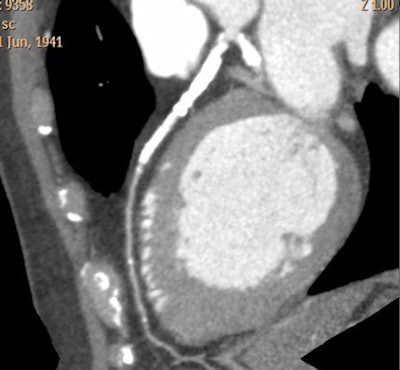

![]() |

| CTA interpretation is complicated by heavy coronary artery calcification; flow analysis could potentially aid diagnosis in such cases. All images courtesy of Dr. Henning Bovenschulte. |